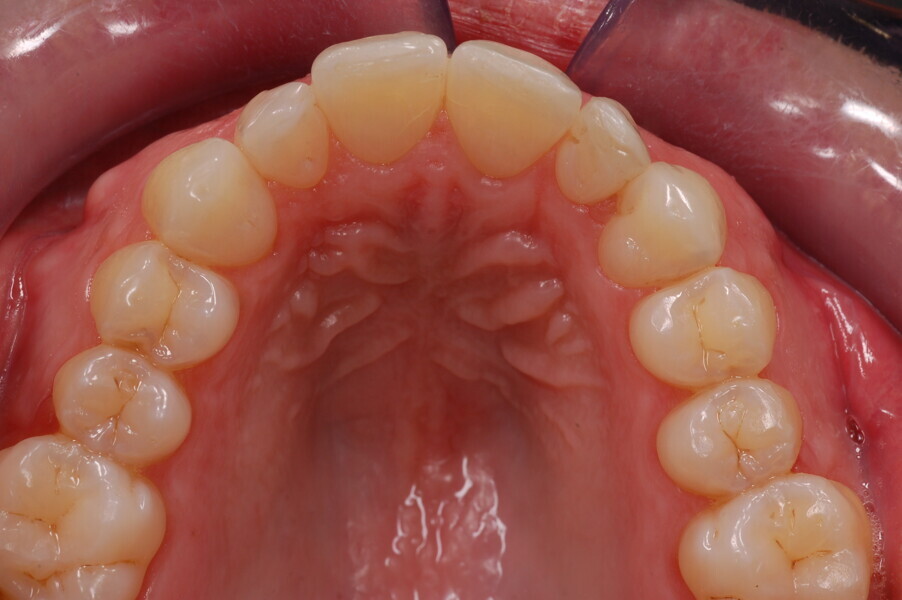

After 26 months, the HAT auxiliary was removed, and few refinement aligners for the final mandibular alignment were delivered to the patient. After a total treatment time of 28 months, composite restorations were performed on the maxillary incisors, and the patient received two rigid retention aligners for night-time wear.

Treatment results

The post-treatment extra-oral photographs showed the improvement of the smile aesthetics (Figs. 51–58). A solid bilateral Class I occlusion was achieved with normal overjet and overbite. The dental arches were well aligned and levelled, and even the severe rotation of the mandibular left second premolar was corrected with aligners only. The post-treatment cephalometric evaluation (Fig. 59) showed an improvement in the anteroposterior position of the mandibular incisors (Li–APog: 2.21 mm) while maintaining the facial height (lower facial height: 53.12°; facial axis: 83.96°; Table 1).

The panoramic radiograph showed that the root of the mandibular right lateral incisor had been uprighted by the HAT auxiliary, without any major root resorptions, while achieving good parallelism with the adjacent teeth (Fig. 60). The impacted mandibular third molars were still present because the patient refused to have them extracted.